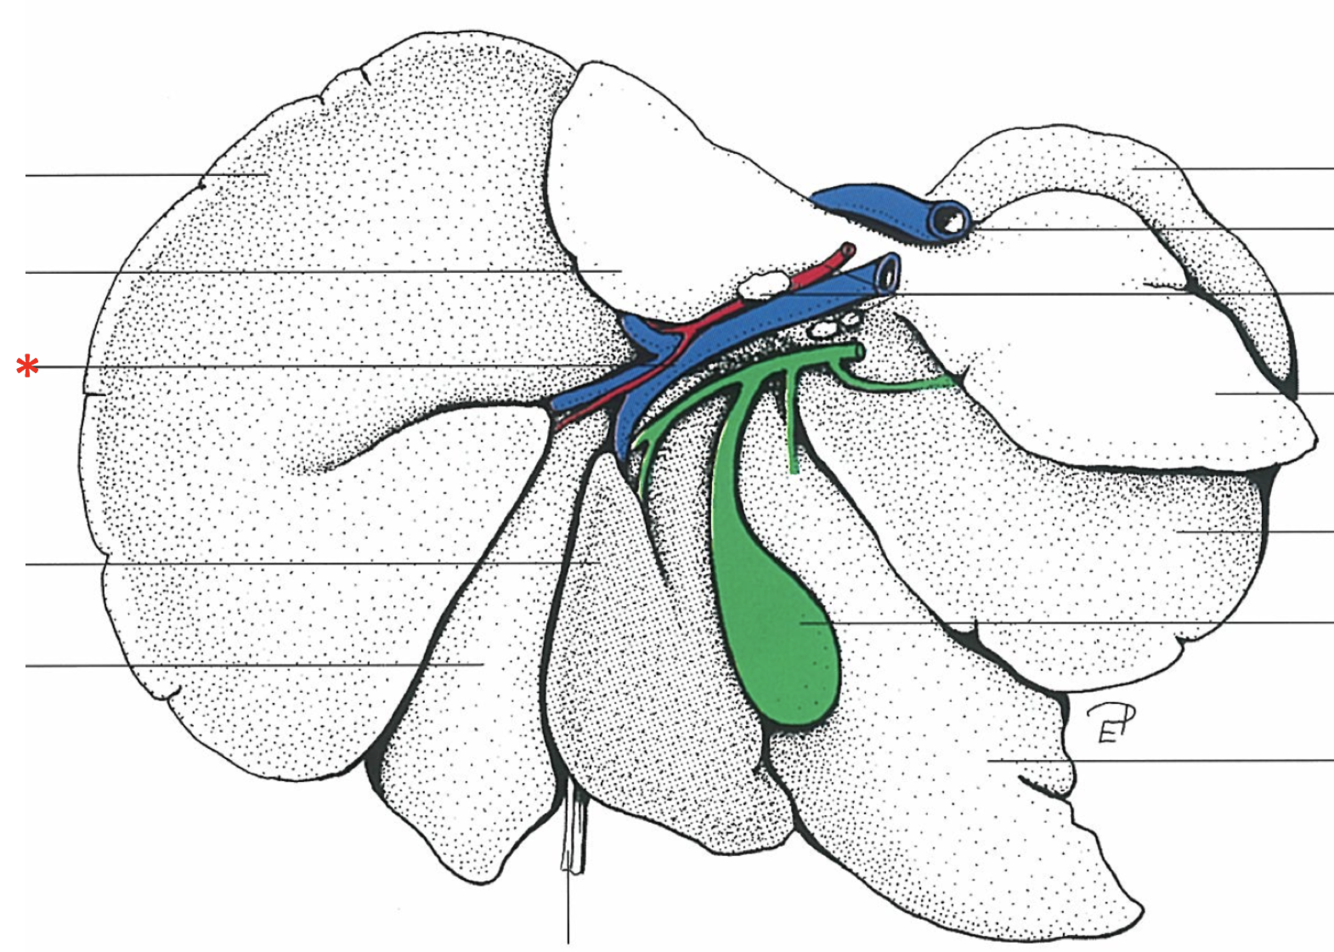

Lig. hepatogastrica

16

Lig. hepatoduodenalis

- Adjacent to ostium pyloricum

Lig. triangulare sinistrum

Lig. triangulare dextrum

Lig. hepatorenale